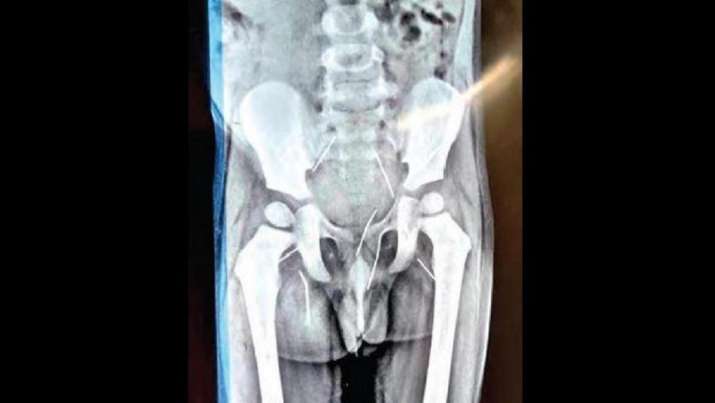

Telangana: Doctors find 11 needles inside 3-year-old's back, private parts; shocking details emerge

In a spine chilling incident, doctors found around 11 needles inside the body of a toddler in Wanaparthy district. A three-year-old boy, who was unwell for the last six months, was taken to hospital by his parents after spotting a needle poking out of his back.